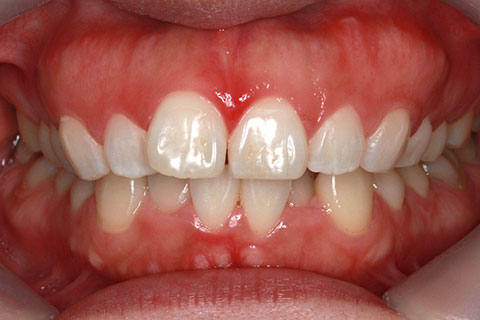

矯正期間18ヶ月

フルリンガル矯正2(上下の歯を舌側矯正で治療)

治療前

治療中

治療後

- 年齢・性別

- 42歳男性

- 治療期間

- 1年6ヶ月

- 抜歯

- なし

- 治療費

- 120万円(税込み)

- 備考

- マルチブラケットを用いた矯正治療

- 治療内容

- 反対咬合をフルリンガル矯正治療にて改善

- 施術の副作用(リスク)

- 表側矯正と比較して、歯根の角度を確立する「トルク」の力がかかりにくい。